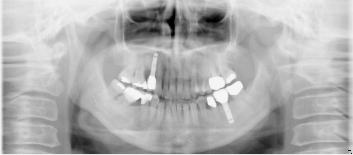

60歳男性

60代男性

治療前 |

治療後 |

歯の根が割れて保存不可能だったため抜歯し、 |

|